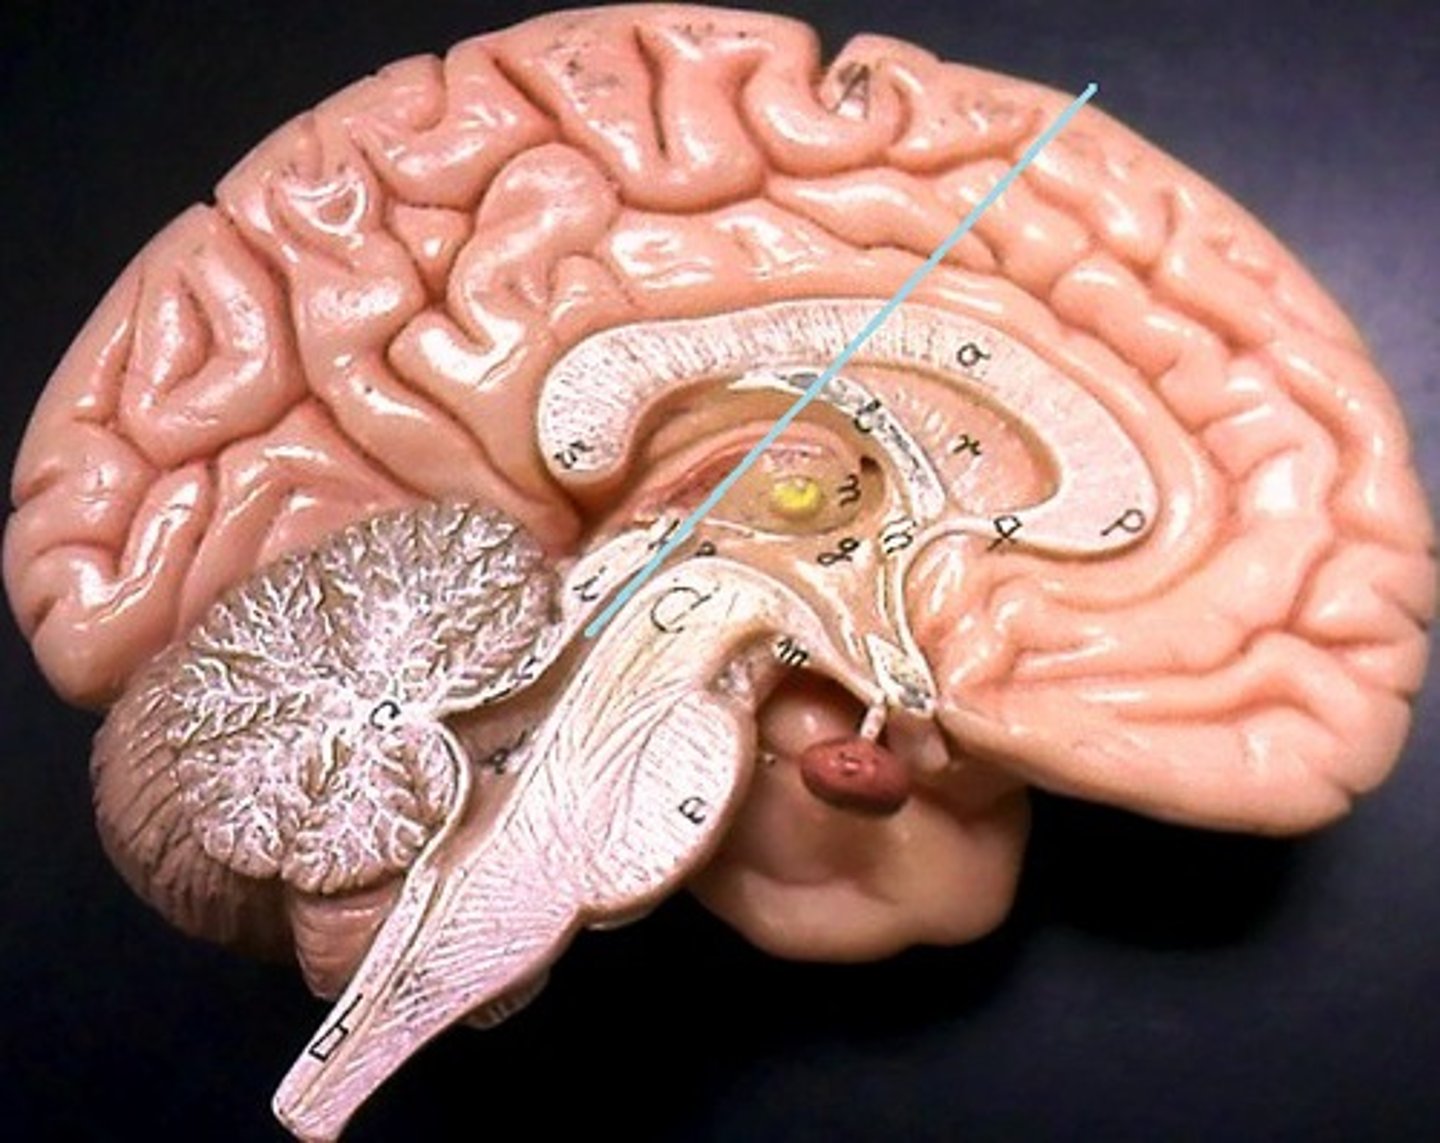

brainstem

cerebellum

cerebrum

medulla oblongata

lateral ventricles

midbrain

pons

thalamus

corpus callosum

cerebral aqueduct (brainstem)

fourth ventricle

hypophysis (pituitary gland)

pineal gland

third ventricle